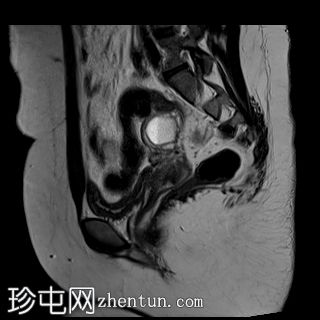

矢状位

T2加权像

3.jpg

双侧卵巢位置接近(卵巢相吻),左侧卵巢内可见一边界清晰的囊性病变,大小约3.1 × 2.7 × 2.9 cm,T1加权像呈高信号,T2加权像可见暗点征及内部暗点征。以上MRI特征符合卵巢子宫内膜异位囊肿的诊断。

右侧卵巢可见一囊肿,大小约为 2.8 × 2.0 × 2.2 cm,T1 加权像呈高信号,囊内可见液-液平面,提示囊内含有不同时期的出血性物质。由于对侧卵巢存在典型的子宫内膜异位囊肿,且该囊肿无强化,影像学表现强烈提示为另一子宫内膜异位囊肿。

双侧卵巢均可见多个小卵泡。

子宫大小、轮廓及信号强度均正常,子宫内膜分区结构完整。未见局灶性肌层病变,子宫内膜厚度在正常范围内。

左侧盆腔可见少量游离液体。

双侧卵巢囊性病变,MRI 表现符合子宫内膜异位囊肿的特征,左侧较大。未见强化壁结节或实性成分,提示无恶性转化。